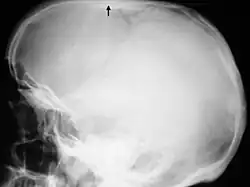

Hiperostoza korowa (łac. hyperostosis corticalis generalisata) – grupa wrodzonych chorób kości, w których obrazie klinicznym występuje uogólnione, symetryczne stwardnienie śródkostne. Opisano do tej pory cztery postaci hiperostozy korowej, różniące się obrazem klinicznym, etiologią i sposobem dziedziczenia: